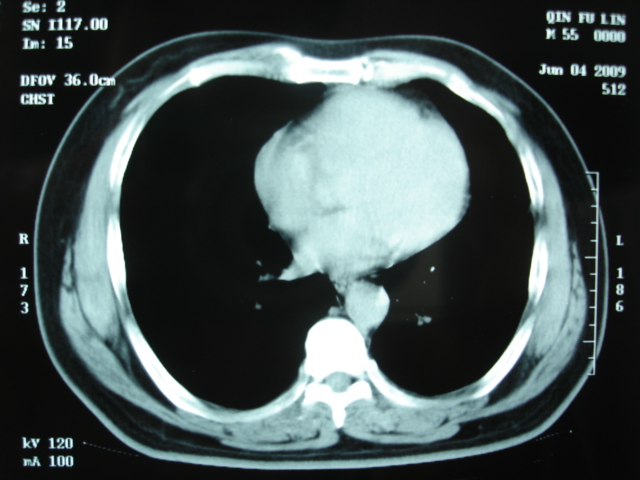

第三次ct2009.8.21

病灶与胸膜成直边征,考虑炎症假瘤可能性大。

考虑左肺上叶炎症感染(炎性假瘤可能)。

考虑 左肺上叶炎症感染 [炎性假瘤可能性大]。

考虑左肺上叶炎症感染,以炎性假瘤可能性大。